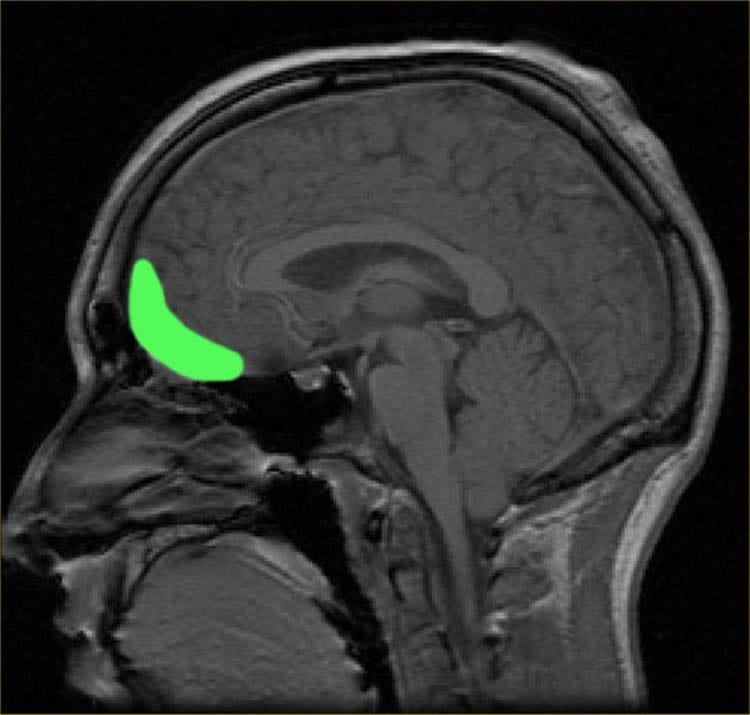

“When participants imagined themselves shooting civilians compared to soldiers, greater activation was found in the lateral orbitofrontal cortex (OFC), an important brain area involved in making moral decisions,” Dr Molenberghs said.

“The more guilt participants felt about shooting civilians, the greater the response in the lateral OFC. When shooting enemy soldiers, no activation was seen in lateral OFC.”

Despite moral prohibitions on hurting other humans, some social contexts allow for harmful actions such as killing of others. One example is warfare, where killing enemy soldiers is seen as morally justified. Yet, the neural underpinnings distinguishing between justified and unjustified killing are largely unknown. To improve understanding of the neural processes involved in justified and unjustified killing, participants had to imagine being the perpetrator whilst watching ‘first-person perspective’ animated videos where they shot enemy soldiers (‘justified violence’) and innocent civilians (‘unjustified violence’). When participants imagined themselves shooting civilians compared with soldiers, greater activation was found in the lateral orbitofrontal cortex (OFC). Regression analysis revealed that the more guilt participants felt about shooting civilians, the greater the response in the lateral OFC. Effective connectivity analyses further revealed an increased coupling between lateral OFC and the temporoparietal junction when shooting civilians. The results show that the neural mechanisms typically implicated with harming others, such as the OFC, become less active (TPJ) when the violence against a particular group is seen as justified. This study therefore provides unique insight into how normal individuals can become aggressors in specific situations.